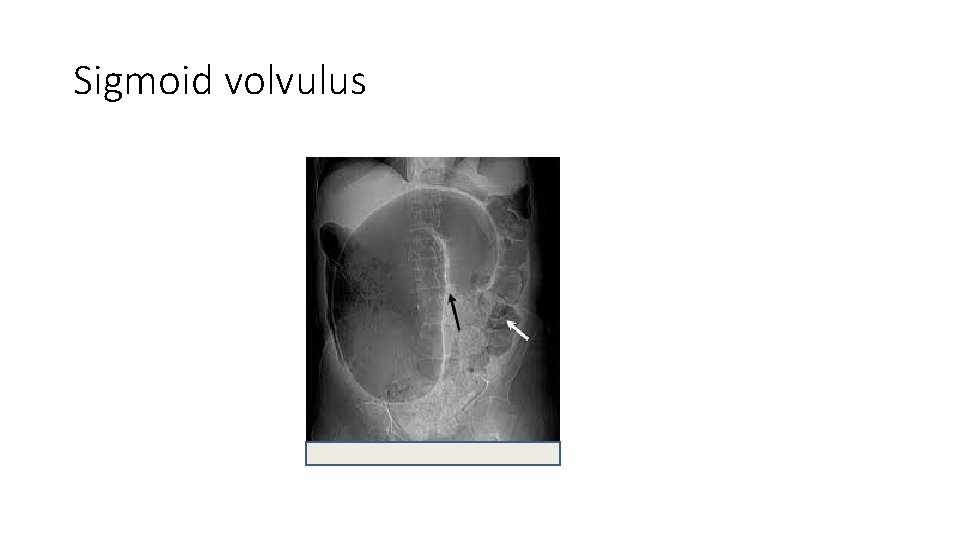

Plain radiographs • An upright chest radiograph is useful to screen for free air which would suggest perforation. • Flat and upright abdominal radiographs can help distinguish severe constipation from bowel obstruction. • Plain films may also help localize the site of obstruction (large vs small bowel). • Sigmoid or cecal volvulus may have a kidney-bean appearance on the abdominal films • Intramural air is an ominous sign that suggests colonic ischemia. • The absence of free air does not exclude perforation

Sigmoid volvulus